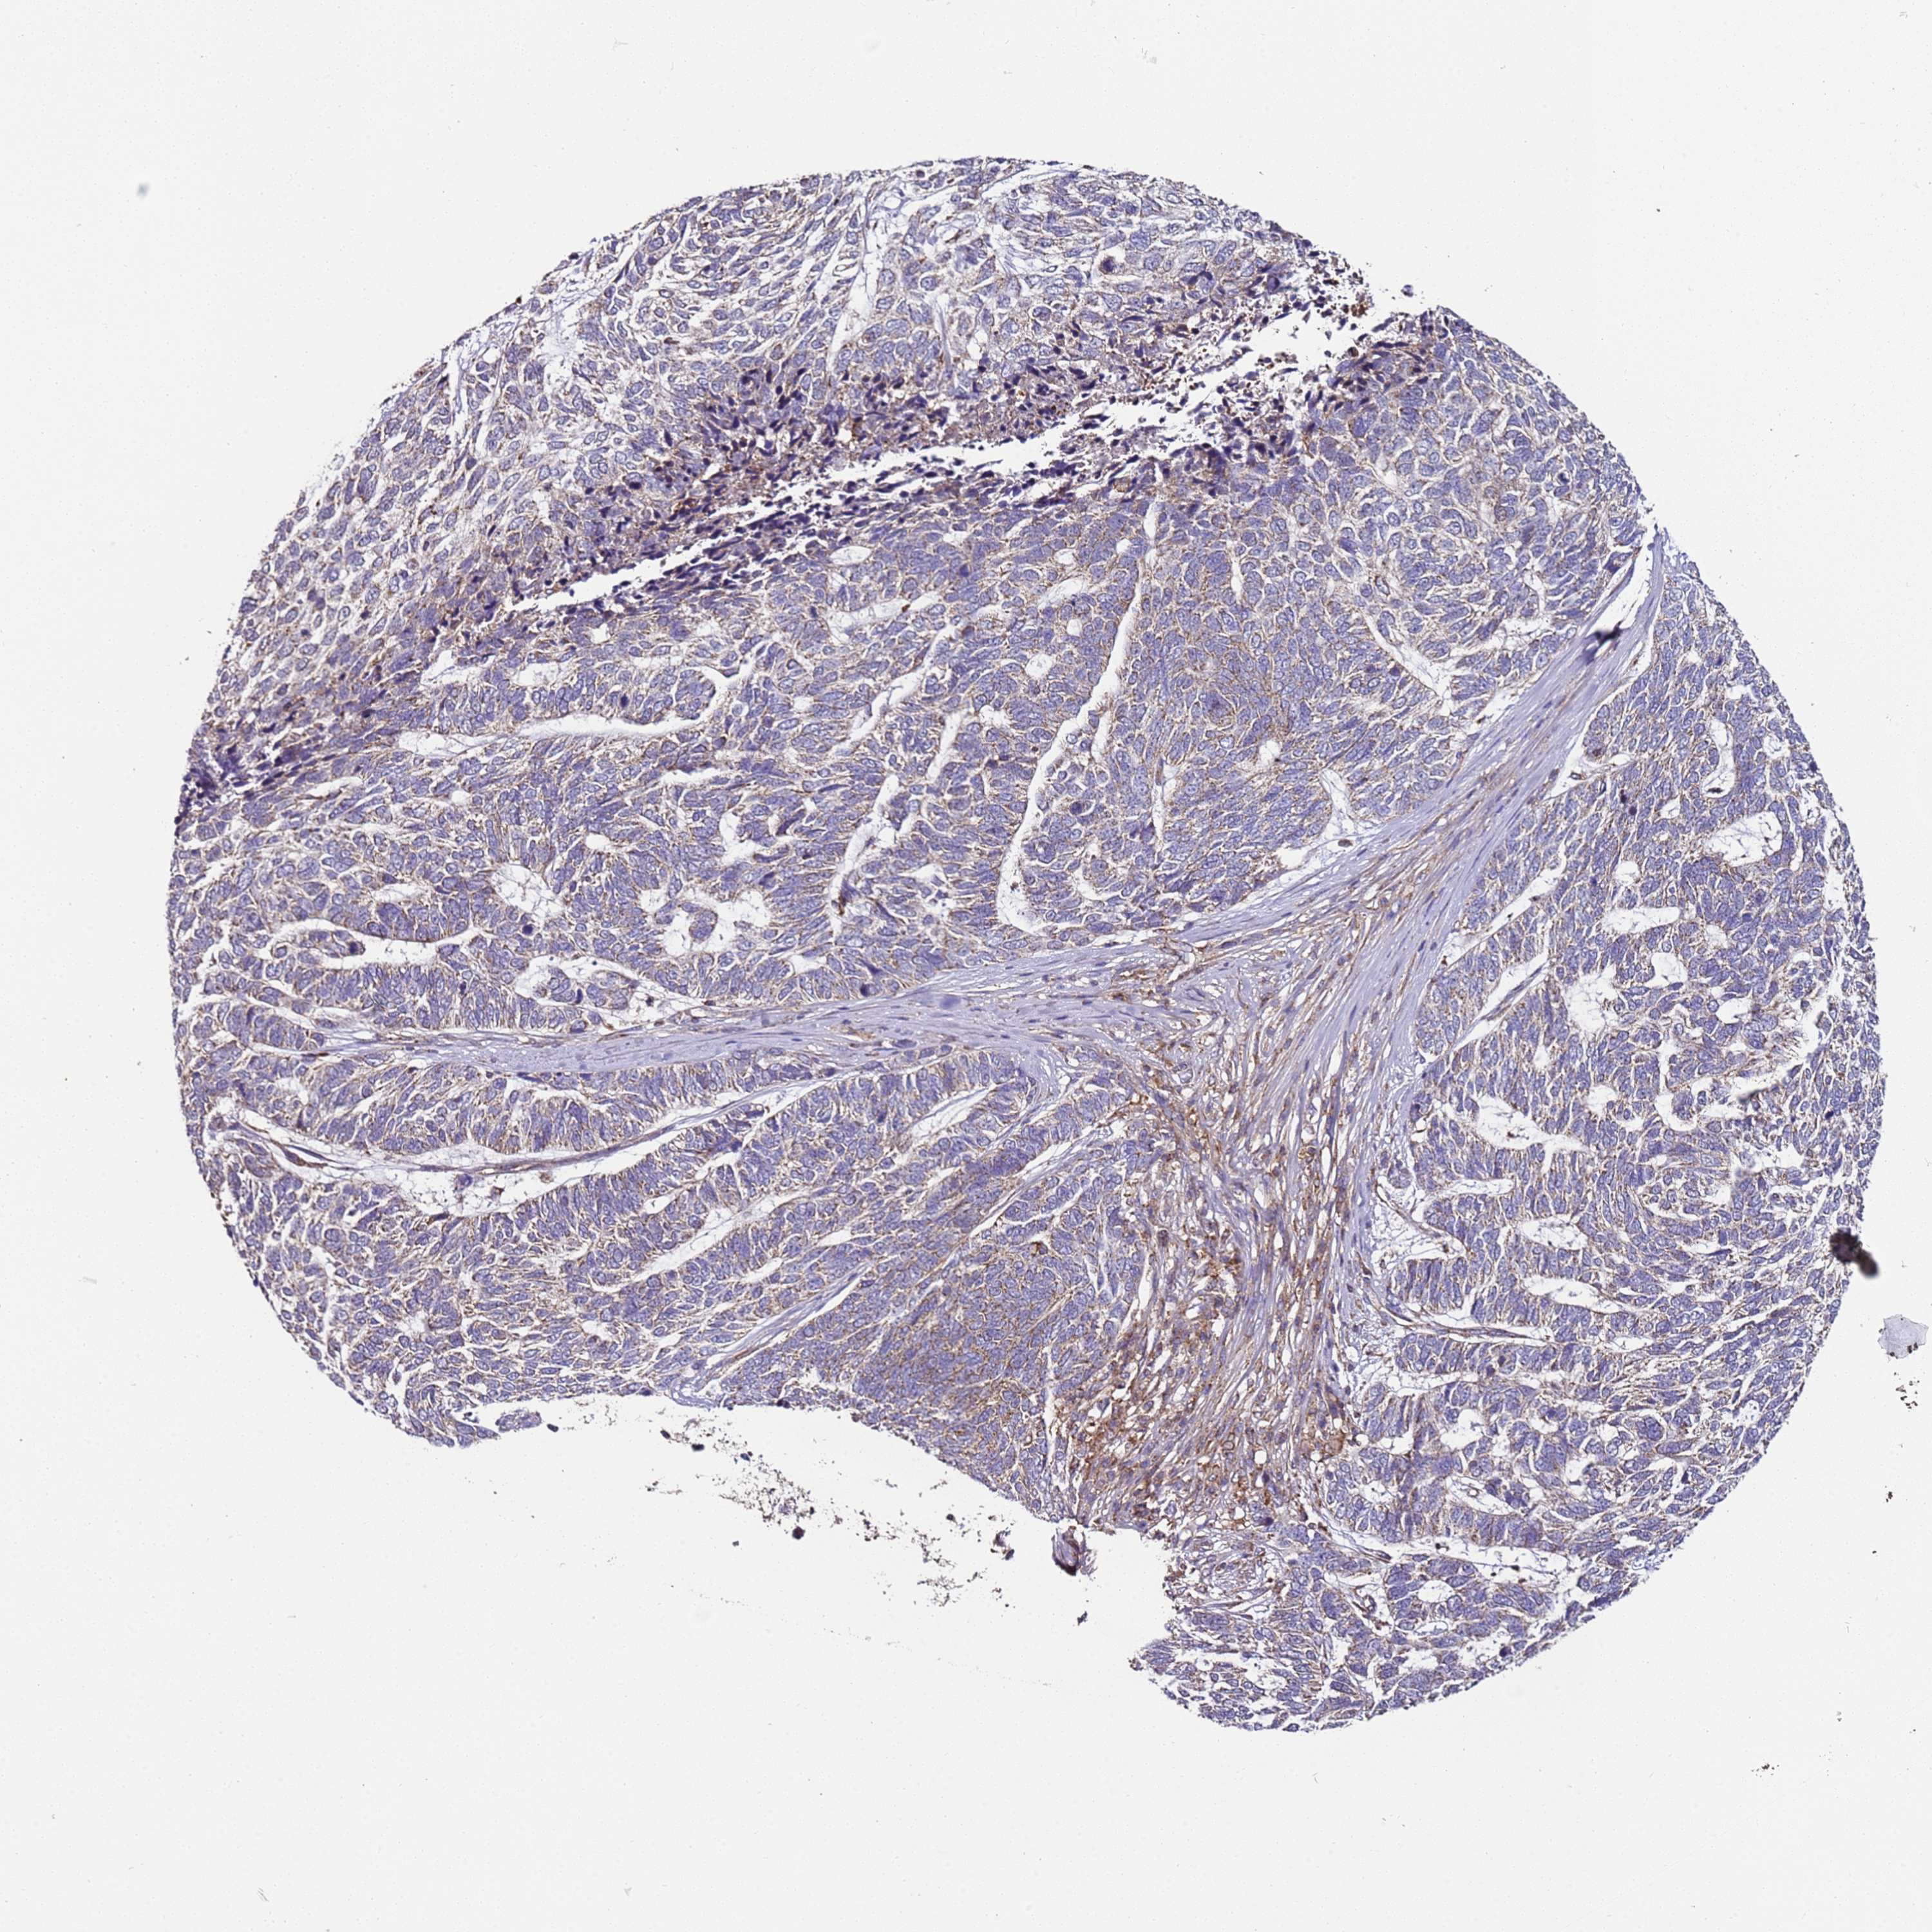

SKIN CANCER - Protein expressioni

A mouse-over function shows sample information and annotation data. Click on an image to view it in a full screen mode. Samples can be filtered based on level of antibody staining by selecting one or several of the following categories: high, medium, low and not detected. The assay and annotation is described here.

Each image is clickable and will lead to virtual microscopy that enables deeper exploration of all samples and also displays staining intensity scores, fraction scores and subcellular localization as well as patient and tissue information for each sample.

Antibody HPA046795

Staining

High

Intensity

Strong

Quantity

>75%

Location

Nuclear

Squamous cell carcinoma, NOS